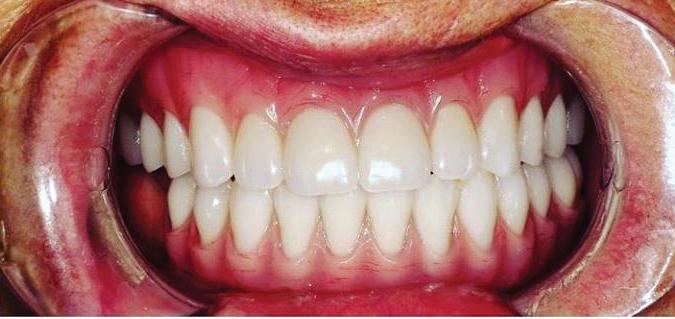

Submitted By Sivakumar Sreenivasan, DMD, MDS Dental Implant Center of Rockville

Can just four implants replace all of the teeth on the top or the bottom of your mouth? Thanks to advances in dental implant technology, that answer is a resounding yes.

Believe it or not, tooth loss is extremely common among adults, especially as we age. In fact, more than 35 million people in America are missing all of their upper and/or lower teeth. Rather than living with the discomfort and hassles of dentures, many people are opting for what is called “all-onfour” dental implant restoration.

All-On-Four:

One Full Arch Of Teeth, Four Dental Implants

To fully understand this remark-

A Reason To Smile Again All-On-Four

able technique for replacing teeth, you should first understand what a dental implant is. An implant is a small titanium screw that fits inside your jawbone and replaces the root-part of a missing tooth. Minor surgery is required to insert the implants. Once the implant is in place, a crown is attached to give you a highly realistic-looking and functional prosthetic tooth.

Here’s where it gets really interesting: You do not need a dental implant for each and every one of your missing teeth. All you need is four precisely placed implants on the top of your mouth, and four on the bottom, to restore your full smile. That’s the beauty of the all-on-four. And because the implant is made of titanium, it has the unique ability to fuse to living bone and function as part of it. So eventually, the dental implant becomes part of the jawbone and serves as a strong, long-lasting foundation for your new teeth.

What’s The All-On-Four Dental Implant Procedure Like?

It can be scary to get implants for the first time. Most of that fear is probably due to the uncertainty, so here is the step-by-step process for getting an All-On-Four dental implant.

First, your dentist will want to make sure your comfortable, so either local or general anesthesia will be administered.

Second, the dentist or surgeon will prepare your mouth for the implants, which involves removing your remaining teeth that are failing. They will then remove any diseased or infected tissue from your jaw and gums.

Besides ensuring that your implants are permanently fixed in place, this bone fusion has another important benefit: it prevents future bone loss in the jaw. This helps to maintain a more youthful facial structure – and better oral health. But perhaps the biggest surprise about the all-on-four is how quickly it can transform your life.

After the implants have been placed, they will thoroughly clean the surgical sites and suturing all the incisions. Then you’ll be taken to a recovery room where you can relax and take time to wake up from the anesthesia.

How Do You Know If The All-On-Four Procedure Is The Right Option For You?

At your All-On-Four consultation, you’ll receive a 3D CT Scan. This scan will help determine if you need implants and assist your doctors in creating your treatment plan. So if you want to learn more about dental implants, simply schedule a consultation with an All-On-Four provider. It’s the best way to find out how dental implants can change your life.

Next, they will begin the implantation process. This means they will insert the titanium screws into your jawbone. Most likely, they will place two implants toward the front of your mouth and two towards the back of your mouth so the “anchors” can evenly bare the force of the denture.

301-805-6805 16 | Your HEALTH Magazine All-On-4: Same Day Smiles CALL TODAY TO GET YOUR OLD SMILE BACK! 301.294.8700 Dental Implant Center of Rockville 77 South Washington Street, Suite #205 Rockville, MD 20850 • www.DrSreeni.com Courtesy 3D Planning For Implants When patients bring a 3D scan with them to or have one taken in the office. Appointment needs to be scheduled before May 15, 2024 Missing Teeth or Tired of Wearing Dentures? Thanks to advances in dental implant technology, just four implants can replace all of the teeth on the top or the bottom of your mouth.